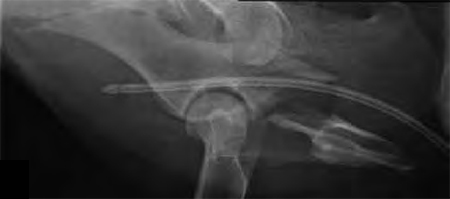

A 4-year-old Gordon setter suffered a road traffic accident and sustained multiple pelvic fractures.

(Case provided by Michael Kowaleski, North Grafton, USA)

A 7-hole 3.5 mm LC-DCP was applied and two screws were inserted into the sacral body to improve fixation strength in the cranial ilial segment. This bone is quite thin thus note that the screws #1 and #2 are quite short, screws #3 and #4 are the sacral screws and are much longer; the fracture is between screws #4 and #5 (see figure 4a-b)). The opacity on midline in the x-rays is a urinary catheter.